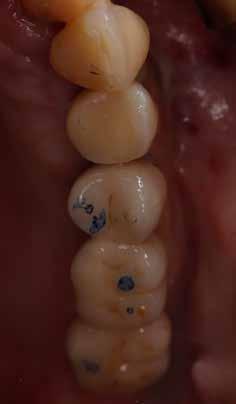

A fogpótlás készítésének lépései

Hathetes gyógyulás után a lágyszövetek kiválóan gyógyultak, és minden implantátum megfelelően osszeointegrálódott, amelyet a radiológiai vizsgálat is megerősítetett (9. és 10. ábra).

Nyitott kanalas lenyomatvételi fejeket csatlakoztattunk az implantátumokhoz, és elasztomer lenyomat-anyagot fecskendeztünk köréjük és a lenyomatkanálba, hogy egyfázisú lenyomatot vegyünk. A minta laboratóriumi elkészítését követően a kimart vázra kerámia leplezés került, amelyet megfelelő festéssel tettek még természetesebbé. Ezt követően a pótlást közvetlenül az implantátumokhoz csatlakoztattuk, majd ellenőriztük a kontaktpontot és az okklúziót. Minden csavart 35 Ncm-es nyomatékra húztunk, majd a csavarnyílásokat teflonszalaggal és fényre kötő kompozittal zártuk (11. ábra).

A végső röntgenfelvételen láthatjuk az osszeointegrálódott implantátumokat, valamint a stabil kresztális gerincet az azonnal behelyezett, a rövid és a ferde, a tuberben elhorgonyzott implantátum körül (12. ábra).

A páciens teljesen elégedett volt az esztétikai és a funkcionális eredménnyel is, továbbá lenyűgözte a kezelés rövidsége, valamint a minimálisan invazív megoldása.